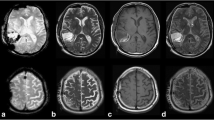

Intracranial air was noticed in every patient. EPI DWI presented with corresponding artifacts in every case. In more detail, air was seen as frontal pneumocephalus in 39 patients, in the resection cavity in 33 cases and in the ventricular system in 16 cases. An illustrative case showing the benefits of STEAM DWI is demonstrated in Fig. 4.

23-year-old female. Postoperative b = 1000 s/mm2 images (left) and apparent diffusion coefficient (ADC) maps (right) obtained by EPI DWI (top) and STEAM DWI (bottom) 40 h after resection of an infratentorial arachnoid cyst with compression of the brain stem. In EPI DWI only hyperintensities (arrows) of the dorsal mesencephalon caused by susceptibility artifacts were noticed. An infarction could not be excluded. In STEAM DWI air (asterisk) and the compression of the brain stem can be detected. An infarction of the mesencephalon could be excluded

More specifically, the air in the resection cavity was in the form of a small microbubble (AAR 1) in 5 cases. In 28 patients (24 patients AAR 2, 4 patients AAR 3), EPI DWI was distorted by air artifacts in the resection cavity, especially in very early postoperative controls (< 24 h). Table 2 illustrates the distribution of air and blood artifacts.

81-year-old patient. Postoperative diffusion weighted images with b = 1000 s/mm2 (left) and apparent diffusion coefficient (ADC) maps (right) obtained by EPI DWI (top) and STEAM DWI (bottom) 42 h after resection of a glioblastoma of the right parieto-occipital region. The patient presented with trapped air in the ventricular system (asterisk ) and the resection cavity (+) and with an infarction of the occipital splenium and the parasagittal occipital lobe (arrows)

In 17 patients with a 3-month follow-up and moderate air artifacts (AAR > 1), EPI DWI detected 36 of 58 lesions (sensitivity 62%, STEAM DWI 100%) compared to the gold standard (3-month follow-up MRI, T2-weighted TSE). In patients with less air artifacts both sequences had a sensitivity of 100% (3-month follow-up MRI, AAR < 2, n = 9, 27/27 lesions).

In 3 of 25 patients with glioblastoma, we detected T2-hyperintense, contrast-enhanced tissue and correlating distorting susceptibility artifacts on EPI DWI. In these cases, STEAM DWI helped to reliably differentiate between a contrast-enhancing residual tumor and a subacute infarct (see Fig. 6 for an example).

77-year-old patient. Postoperative diffusion-weighted images with b = 1000 s/mm2 (left) and apparent diffusion coefficient maps (right) obtained by EPI DWI (top) and STEAM DWI (bottom) 71 h after resection of a left temporal astrocytoma. In EPI DWI the border between infarct area (arrows), cerebrospinal fluid and air is not clear due to geometric distortion, whereas in STEAM DWI the infarct area (arrow) is sharply outlined and even small air bubbles (asterisk) can be detected